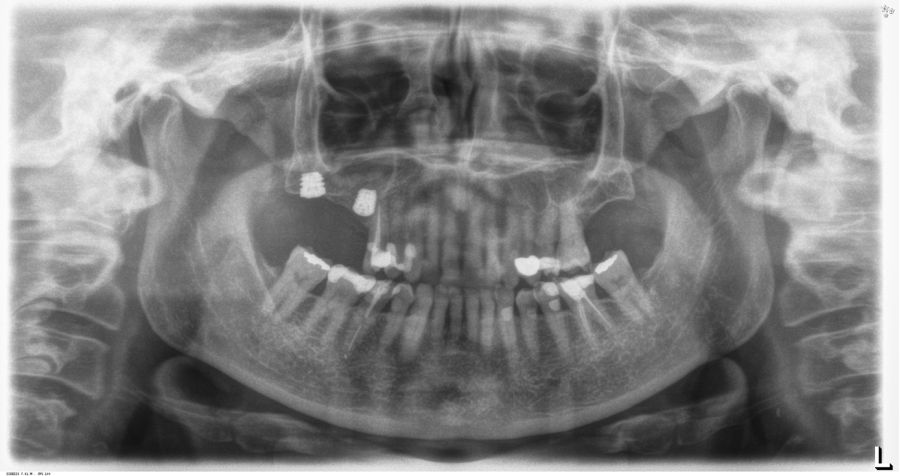

En las Figuras 5-16 se muestra uno de los casos incluidos en el estudio.

La inserción de los implantes fue realizada por un mismo cirujano, mediante la técnica de fresado biológico, a bajas revoluciones, sin irrigación. Con esta técnica todo el hueso recolectado es embebido en PRGF-Endoret durante la cirugía para posteriormente ser utilizado como injerto óseo particulado17-19. El fresado final de la cortical sinusal se realizó con la fresa de corte frontal (ideada para esta técnica) que permite la retirada del suelo del seno maxilar sin dañar la membrana de Schneider6-7. Una vez la membrana es accesible mediante la perforación crestal, se despega, se inserta el implante con el motor quirúrgico fijado a 25 Ncm y 25 rpm finalizando la inserción del implante con la llave dinamométrica (Figura 1). El implante eleva lentamente la membrana a la vez que es insertado en el neo-alveolo.

Una vez finalizada la cirugía se realiza una radiografía periapical con paralelizador, que se utilizó como punto de partida. Los pacientes acudieron posteriormente para la realización nuevas radiografías de control, tomadas con la misma técnica y sobre las que se realizaron las mediciones necesarias para comprobar la estabilidad y pérdida ósea crestal de los implantes. La medición de la pérdida ósea marginal se realizó en la última radiografía periapical realizada con posicionador de seguimiento. Una vez obtenida la radiografía en formato digital es calibrada mediante un software específico (ImageJ software- Rasband, W.S., ImageJ, U. S. National Institutes of Health, Bethesda, Maryland, USA, https://imagej.net/ij/, 1997-2018) a través de una longitud conocida en la radiografía como es el implante dental. Una vez se introdujo la medida de calibración, el programa informático realiza un cálculo basado en esta medida para eliminar la magnificación, pudiendo realizar mediciones lineales exentas de este error (Figura 2). La pérdida ósea de los implantes fue medida en dos puntos: mesial y distal en cada uno de los casos (Figura 3).

Para la estimación de la ganancia en altura sobre el ápice se realizó un CBCT previo a la carga del implante y al año de carga. Posteriormente, el volumen ganado se monitorizó en las radiografías periapicales al igual que la pérdida ósea crestal.

Fueron reclutados 13 pacientes que cumplieron los criterios de inclusión en los que se insertaron 30 implantes. La edad media fue de 70 +/- 1 años en el momento de la cirugía y 10 de los pacientes fueron hombres. El tiempo medio de seguimiento desde la carga fue de 126 meses (+/- 1,79; Rango 120- 150 meses). Los diámetros, longitudes y posiciones de los implantes se muestran en la Figura 4. La altura media de la cresta residual fue de 4,86 mm (+/-0,97; rango 1,95-5,88 mm). El torque de inserción medio de los implantes fue de 26,45 Ncm (+/- 1,89). Una vez insertados y cargados los implantes, la altura media final fue de 9,68 mm (+/- 2,66; rango 6,74-13,11 mm), lo que supone una ganancia promedio de 5 mm. A los 10 años, se observa una disminución media de la altura ósea ganada en los implantes en conjunto de 0, 29 mm (+/- 0,77).

La media de la pérdida ósea mesial fue de 0,73 mm (+/- 0,75 mm) y la media de la pérdida ósea distal fue de 0,98 mm (+/- 1,2 mm). No existió ningún fracaso en los implantes estudiados, por lo que la supervivencia fue del 100%. Todas las prótesis se rehabilitaron de forma atornillada mediante transepitelial, siendo un 85% de ellas puentes de 2 a 4 unidades y el resto prótesis completas. No se produjeron complicaciones en la técnica quirúrgica en ninguno de los casos estudiados, sin producirse ninguna perforación de la membrana de Schneider.